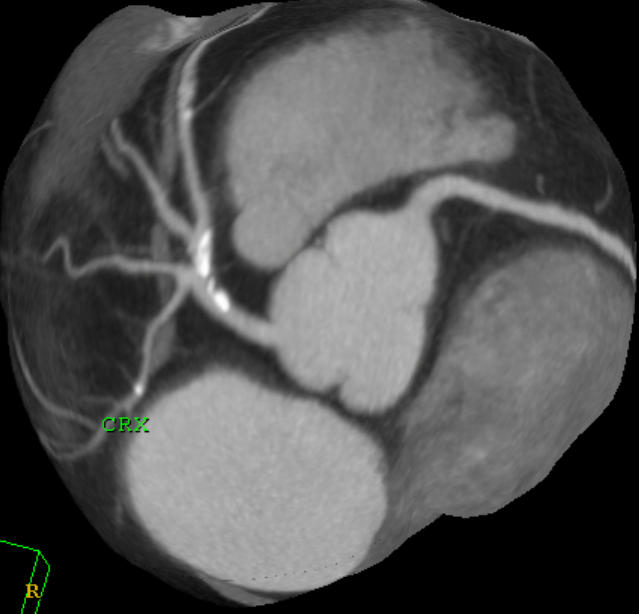

coronaro TC